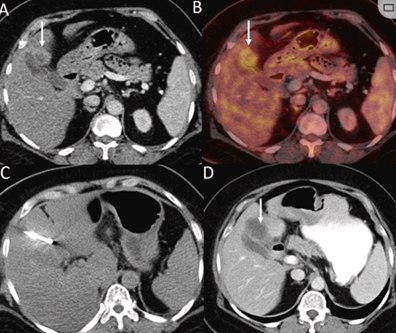

CT引導的冷凍消融

(b) 冷凍消融術(shù)中影像顯示冰球完全覆蓋病變。(c) 19個月后隨訪,沒有發(fā)生局部腫瘤進展。完全消融率為97%(66/68);2名患者均接受了額外的冷凍消融,隨后實現(xiàn)完全消融。平均隨訪期為 12.8 個月(范圍:3-27 個月)。所有患者均接受影像復查(CT 或 MRI)。11個病灶(16.2%)檢測到局部腫瘤進展,6、12和18個月時的累積局部腫瘤進展率分別為4%、8.2%和20.5%。8例出現(xiàn)遠處肝內(nèi)或肝外病變的患者接受經(jīng)動脈化療栓塞、經(jīng)動脈化療栓塞加射頻消融治療或全身化療。